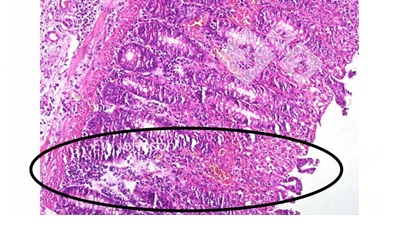

Khi kiểm tra mô bệnh học, thấy có viêm mạch lan toả và nhồi huyết, xuất huyết và huyết khối ở nhiều cơ quan, đặc biệt là phổi, lá lách, hạch bạch huyết, thận, não và ruột. Lymphoid bị phá hủy trong các hạch bạch huyết và lá lách, và hình thành không bào trong các đại thực bào phế nang. Thường gặp hiện tượng hoại tử và loét biểu mô đại tràng (Ảnh 4).

Ảnh 4. Huyết khối mạch máu, nhồi máu, loét niêm mạc đại tràng.